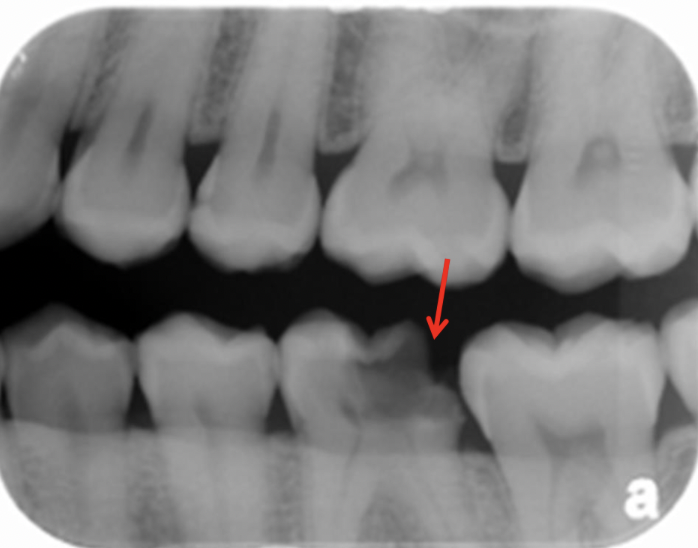

11

A

Moderate caries (MC)

12

13

14

15

Classify the caries: